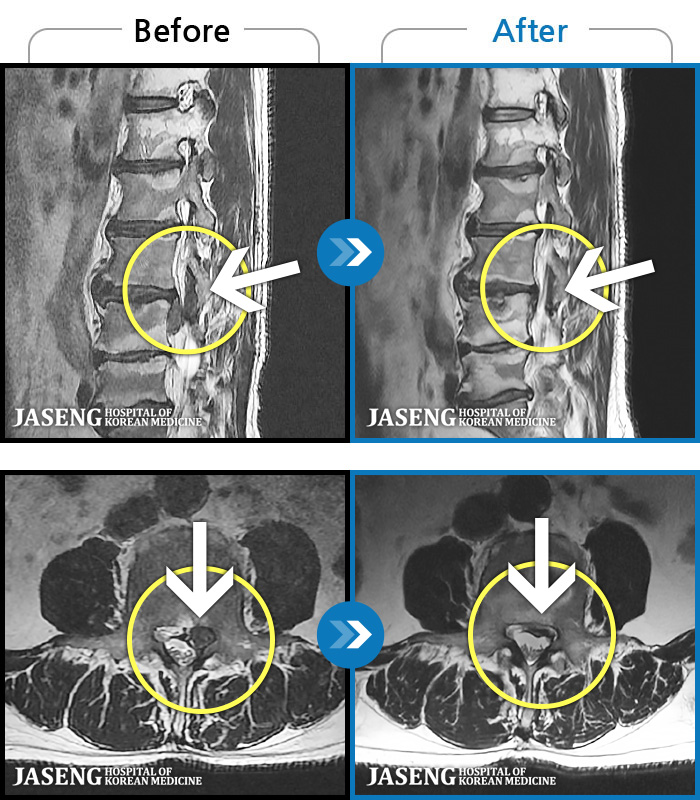

[Կñ:03.04.01~09.11.01]

[_㸮ũ] 㸮 , ٸ ̾ ϼ̽ϴ.

No.1236

ȸ 2,194

2025.09.22